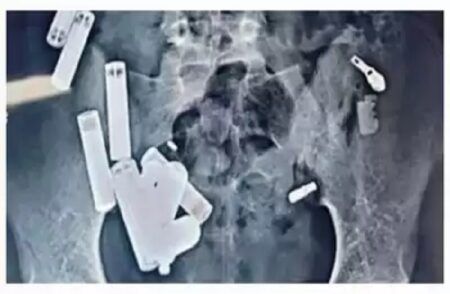

ನವದೆಹಲಿ: ಉತ್ತರ ಪ್ರದೇಶದ ಹತ್ರಾಸ್ನ 14 ವರ್ಷದ ಬಾಲಕ ಆದಿತ್ಯ ಶರ್ಮಾ ದೆಹಲಿಯ ಸಫ್ದರ್ಜಂಗ್ ಆಸ್ಪತ್ರೆಯಲ್ಲಿ ಸಂಕೀರ್ಣ ಶಸ್ತ್ರಚಿಕಿತ್ಸೆಯ ನಂತರ ದುರಂತವಾಗಿ ಸಾವನ್ನಪ್ಪಿದ್ದಾನೆ. ಆತನ ಹೊಟ್ಟೆಯಲ್ಲಿದ್ದಂತ 65…